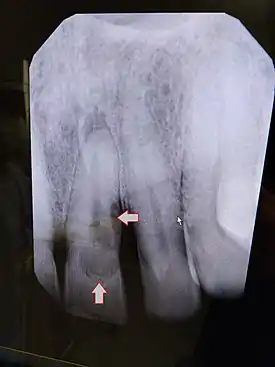

| Post traumatic External tooth resorption 9 | |

| Diagnostic method | Dental examination, X-rays |

External Inflammatory Root Resorption

External inflammatory root resorption may be caused by trauma to the root surface, due to damage to the periodontal ligament (PDL) and/or extended drying following tooth avulsion. Following trauma, dentinal tubules are exposed leading to communication with an infective or necrotic pulp. This leads to an inflammatory process that causes external root resorption.[16]